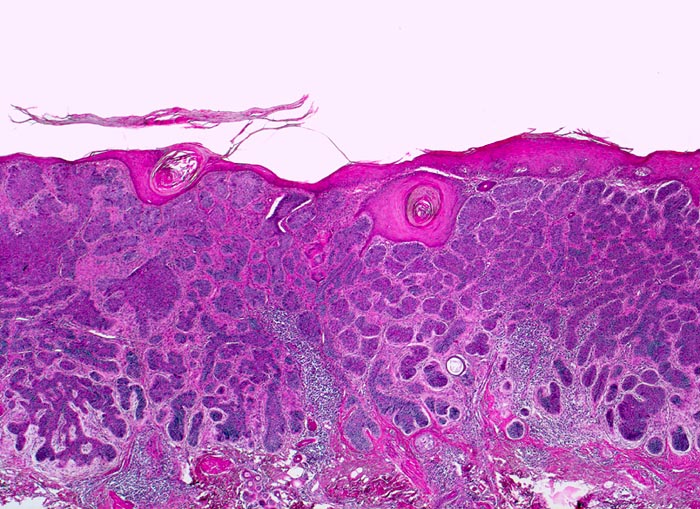

PathoPic – image database / PathoPic ID 5104 - Basaliom

Basaliom

maligner Tumor

Haut, Kopf

Unmittelbar unterhalb der Epidermis liegen kompakte basophile verzweigte expansiv wachsende Zellplatten. Fokale Hyperkeratose der Epidermis. Am Rand des Tumors dichtes chronisches Entzündungsinfiltrat.

Derber weisser, leicht erhabener Knoten an der Nase.

Histologie

25